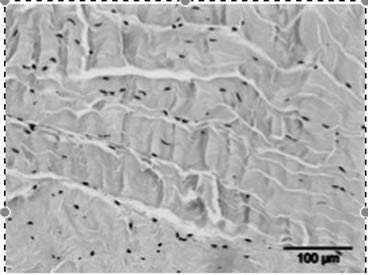

• Het stimuleren van de collageenproductie en het afvoeren van beschadigd collageen, wat resulteert in een verhoogde matrix-turnover.

• Het beïnvloeden van stamcelmigratie en -proliferatie via mechanotransductie.